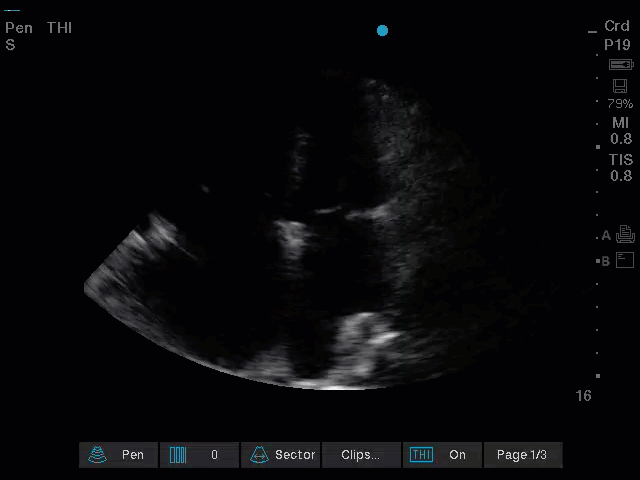

An area that is quite frought with error is the approach, in particular during a cardiac arrest, is to judge whether the RV is dilated as a sign of acute PE. Putting aside the fact that RV frequently becomes dilated during cardiac arrest regardless of the presence of embolus the subcostal view frequently underestimated RV signs as it is generally quite an inferior angle which tends to “shrink” the RV. The views below of the subcostal (left) and A4C (right) are from the same patient which while the RV appears impaired by visual TAPSE in the subcostal views and perhaps moderately enlarged as it is close in size to the LV we see this is a gross underestimate when viewing from the A4C an RV that is dwarfing it neighbour.